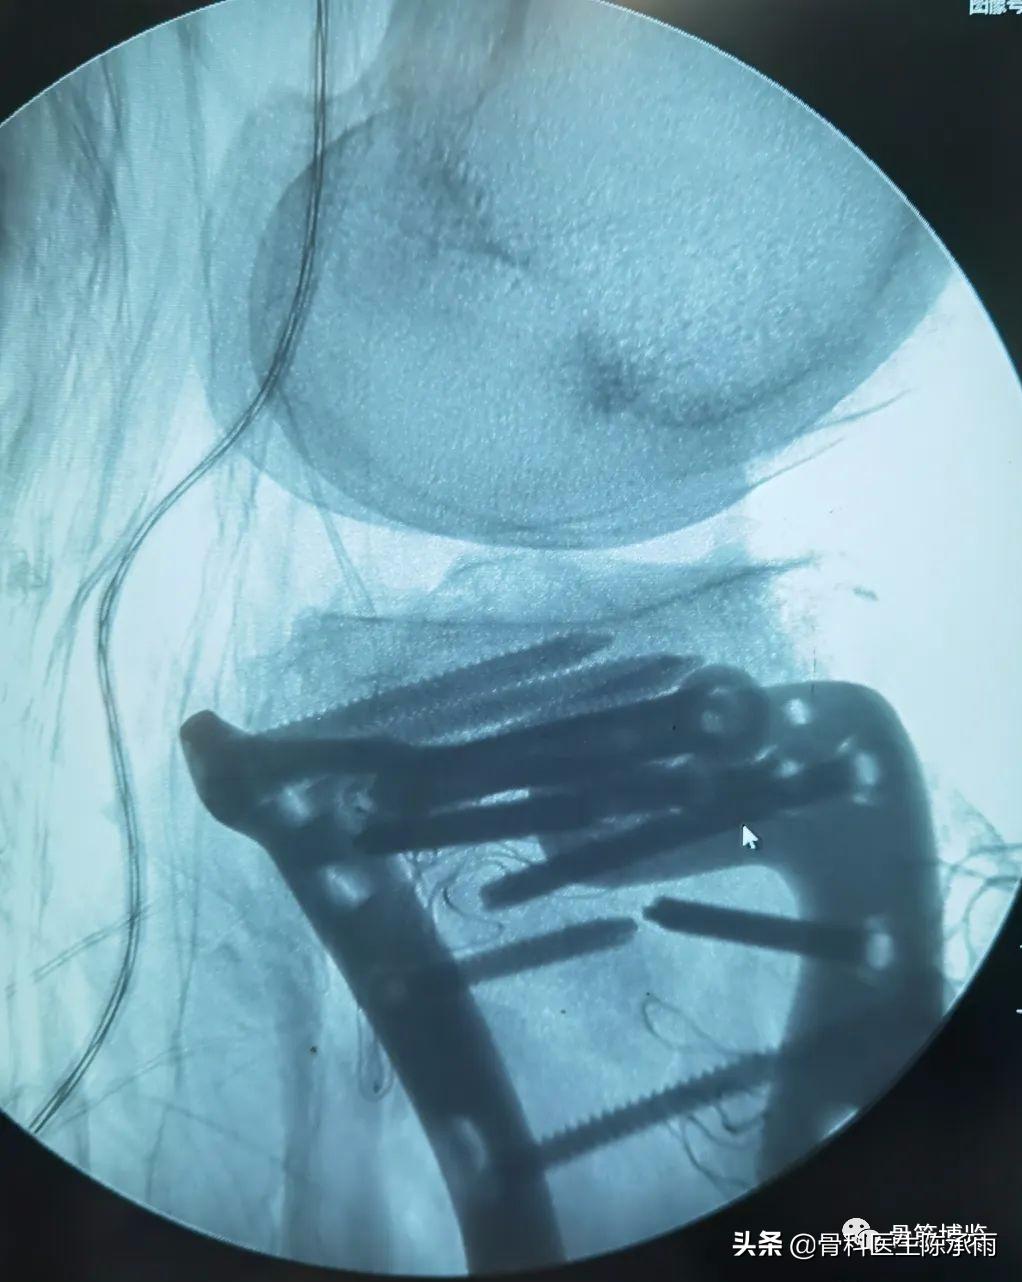

下例胫平台骨折皮肤条件差,内侧板取两端小切口置入内板固定。胫骨结节处撕脱骨折以1枚拉力螺钉固定。